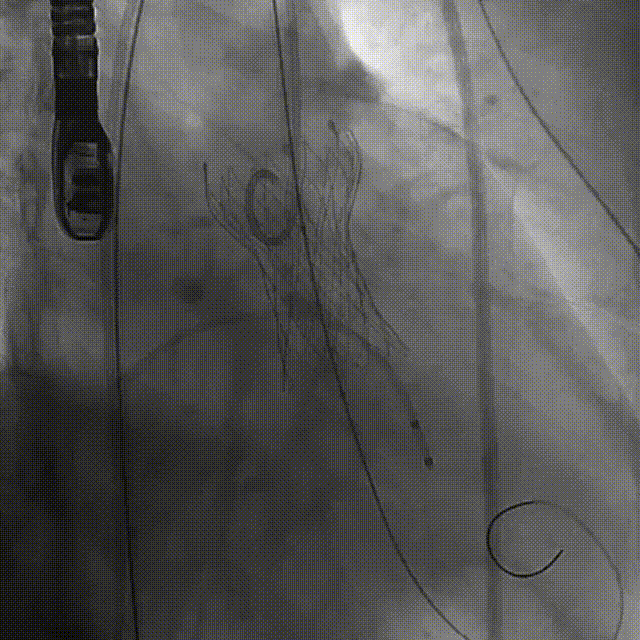

术中影像

释放

最终工作位置

术中及术后未出现相关并发症,瓣膜植入位置符合预期,患者症状得到明显改善,手术圆满完成。

术中综合分析未进行球囊预扩,选择TaurusElite  AV31瓣膜送至主动脉弓,输送系统轻松过弓及跨瓣,精准定位无冠窦最低点,利用可回收功能,术中对位置进行适当调整,大大提升了瓣膜精准释放的几率,保证了手术的安全性,最后使用25mm球囊后扩,优化了瓣膜形态,使患者获得了更大的获益。